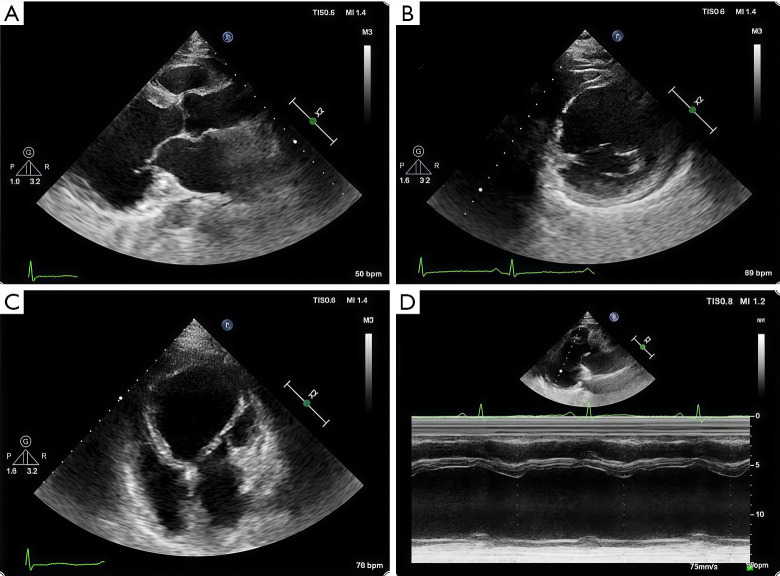

Case description: In this report, we describe a case of secondary syncope in a patient with ALVC who developed right bundle branch block with ventricular tachycardia (RBBB-VT), with VT originating in the left ventricle (LV). Cardiac magnetic resonance (CMR) revealed significant enlargement of the LV, with LV dysfunction. Late gadolinium enhancement (LGE) and fat sequencing revealed that most of the free wall of the LV was replaced by fibrofatty tissue.